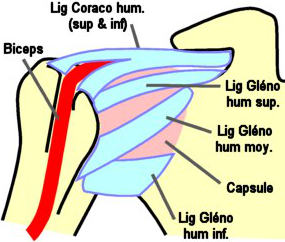

Moyens d'Union

Passifs

-

la

capsule est mince et lâche en BAS ce qui permet un ample mouvement

d'abduction. Elle est renforcée de ligaments en HT, en BAS et en AV.

la

capsule est mince et lâche en BAS ce qui permet un ample mouvement

d'abduction. Elle est renforcée de ligaments en HT, en BAS et en AV.

- en HT, le ligament coraco-huméral : c'est le ligament le plus

résistant de l'épaule. Il est composé de 2 faisceaux (fais. supérieur,

qui part du processus coracoïde et se termine sur le tubercule majeur

(old. trochiter) - fais.

inférieur, de même origine, se termine sur le tubercule mineur (old.

trochin).

- en AV et en ABS, les 3 ligaments gléno-huméraux forment un "Z" est

luttent contre la luxation de l'épaule.

- lig. gléno-huméral supérieur (origine : au dessus de la cavité

glénoïdale et du bourrelet glénoïdien - terminaison : tête au

dessus du tubercule mineur)

- lig. gléno-huméral moyen (origine : bord antérieur du pourtour

de la cavité glénoïdale - terminaison : tubercule mineur, en DD de

l'insertion du sub-scapulaire)

- lig. gléno-huméral inférieur (origine : bord antérieur du

pourtour de la cavité glénoïdale - terminaison : à la partie

antéro-interne du col chirurgical de l'humérus, en DD du tubercule

mineur). Leurs dispositions définissent 2 points de faiblesse :

l'inférieur est le plus faible, le supérieur est renforcé par le

muscle sub-scapulaire (qu'une bourse séreuse protège).

Le

tendon du long biceps est intra-articulaire, mais extra-synovial, il est

contenu dans une gaine de la capsule.

Le

tendon du long biceps est intra-articulaire, mais extra-synovial, il est

contenu dans une gaine de la capsule.